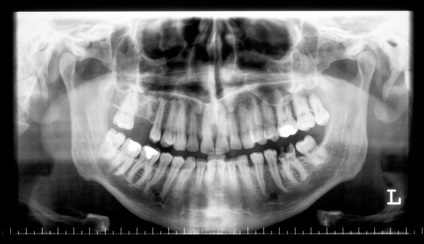

顎関節パノラマ写真撮影・診断

当院では顎関節パノラマ写真の撮影・診断も行っています。上記3DのCT撮影に加え、やはり顎関節パノラマによる診査・診断は重要なポイントです。